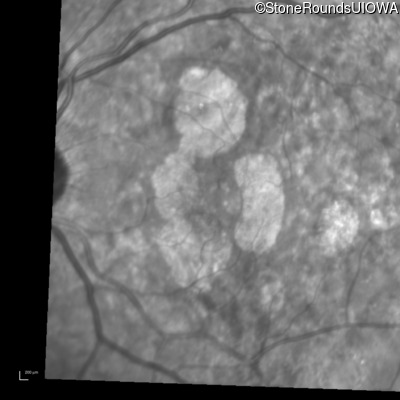

Infrared Fundus Photograph - Left - 20/20 -1

Exemplar